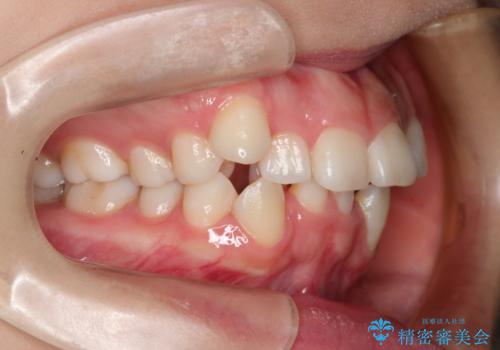

- 前歯のデコボコと上顎の前突感による口の閉じにくさを気にして来院された患者様です。

目立たない装置を希望されたので、上顎が裏側装置のハーフリンガルを選択し、上下左右の小臼歯(計4歯)を抜歯して矯正治療を行うこととしました。